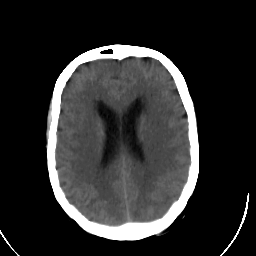

Stroke CT #3 -- Slice #16

[Home][Help][Clinical] Slice 16